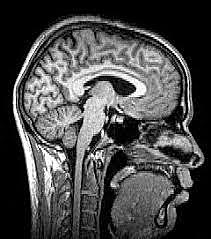

• Resonancia Magnetica

Resonancia Magnetica

Damadian y Lauternur producen la primera resonancia magnetica.